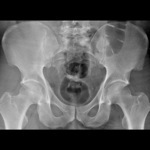

Pelvis

Axial